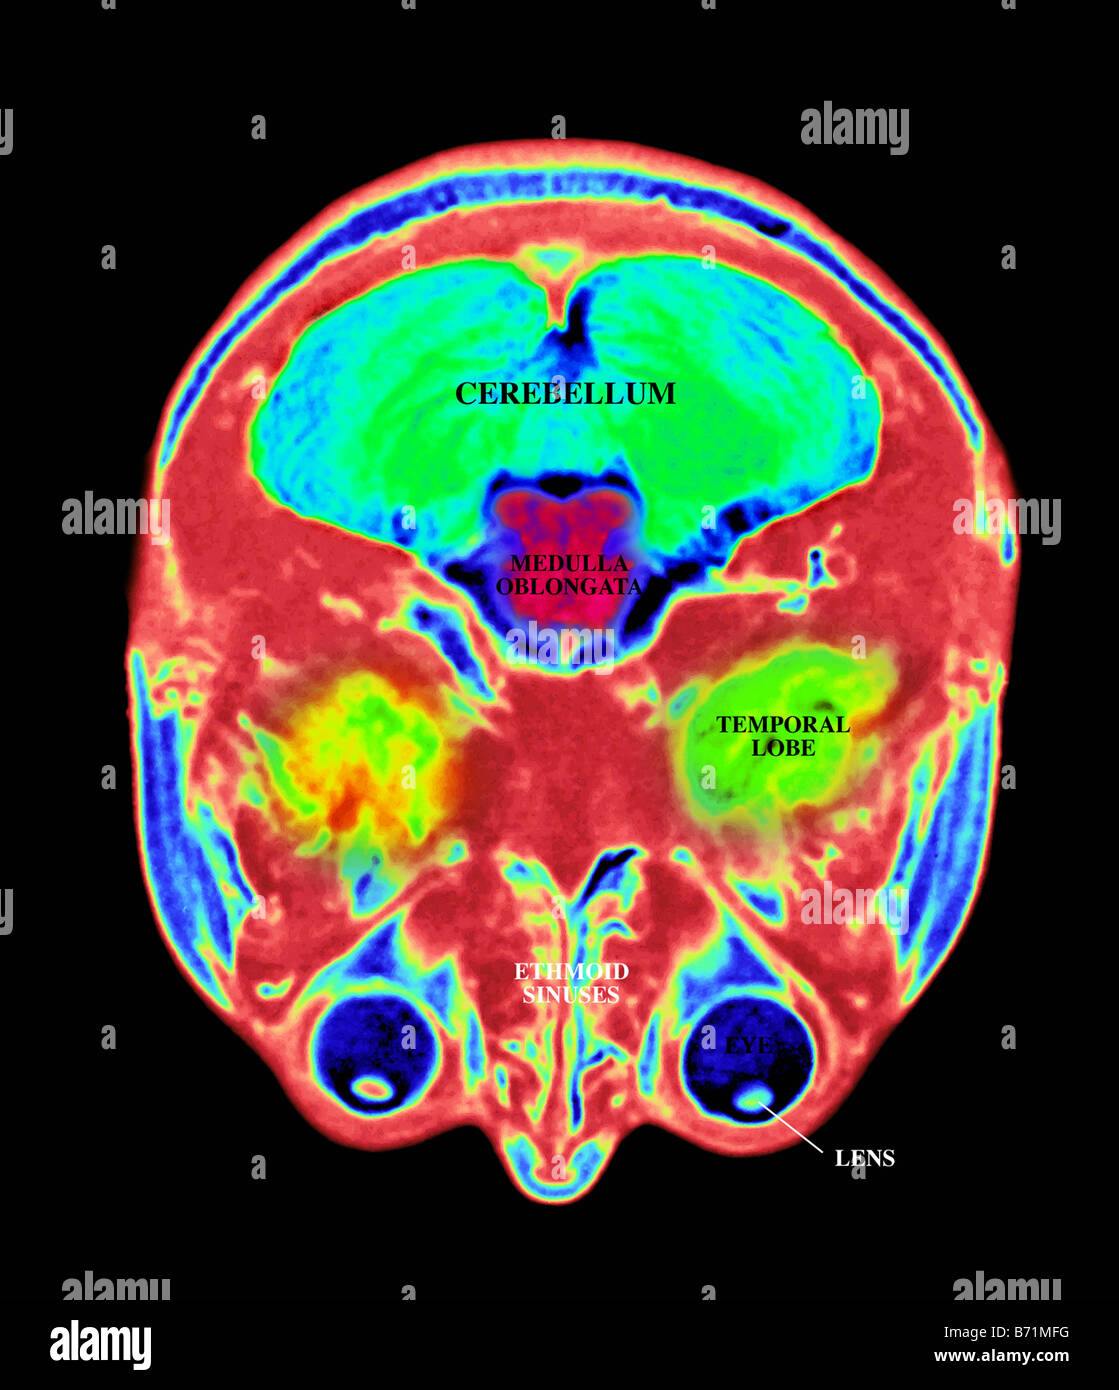

Mri Of The Brain Labeled . the whole brain atlas. 1 article features images from this case. Look at midline image, from bottom to top: essentially normal mri of the brain for reference. This atlas was developed to identify the normal neuroanatomical structures of the entire brain in the mri. Case contributed by maciej debowski. mri brain is a specialist investigation that is used for the assessment of a number of neurological conditions. It is the main method to investigate. this article will explain how to read a brain mri using concrete examples of the mri images of the brain. Key facts about the normal brain mri mri. 72 public playlists include this case.

mri brain is a specialist investigation that is used for the assessment of a number of neurological conditions. this article will explain how to read a brain mri using concrete examples of the mri images of the brain. Case contributed by maciej debowski. Key facts about the normal brain mri mri. 72 public playlists include this case. Look at midline image, from bottom to top: It is the main method to investigate. essentially normal mri of the brain for reference. 1 article features images from this case. the whole brain atlas.